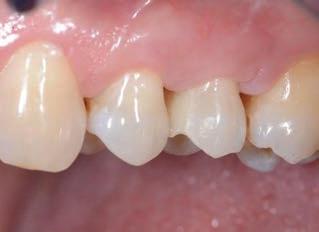

Figure 1: Initial situation. The patient reported generic pain in the second quadrant, where there was a restoration in temporary material on tooth number 25. Figure 2: Initial radiograph showing endodontic dressing that had been present for some months, but the treatment was never completed. Note the depth of the caries lesion and the proximity of the interdental bone ridge, which may represent an obstacle for prosthetic rehabilitation.

This element was not stimulated with the cold test and the radiographic image revealed an incomplete endodontic treatment (Figs. 1-2). The element seemed to present a suitable root length for a conservative restoration, but the apical position of the carious lesion and the proximity of the interdental bone ridge didn’t allow a correct rehabilitation with prosthetic crown, respecting the biological width.2